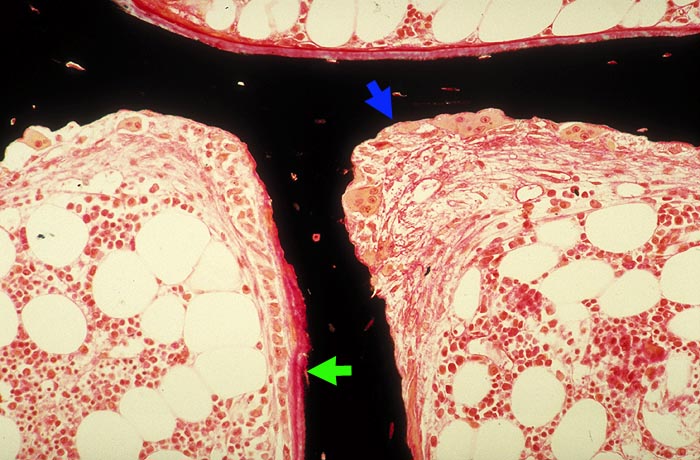

Renale Osteopathie

Knochen, Knorpel, Gelenke

Knochen

Knochen (Wirbelkörper und Discus intervertebralis)

Pathologischer Befund